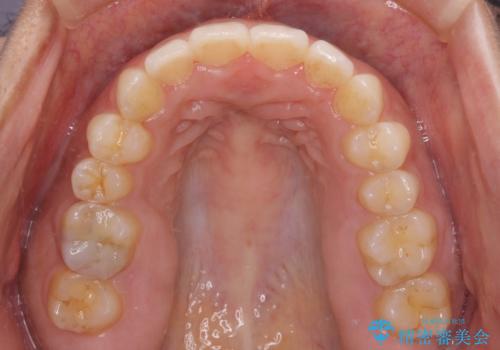

- 上下の前歯のでこぼこを気にして来院された患者様です。

結婚式が近いこともあり、全く目立たない裏側矯正により口元を整えることとしました。

下顎が左側にずれているため、裏側矯正ということもあり咬み合わせを整えるのに時間がかかってしまいました。